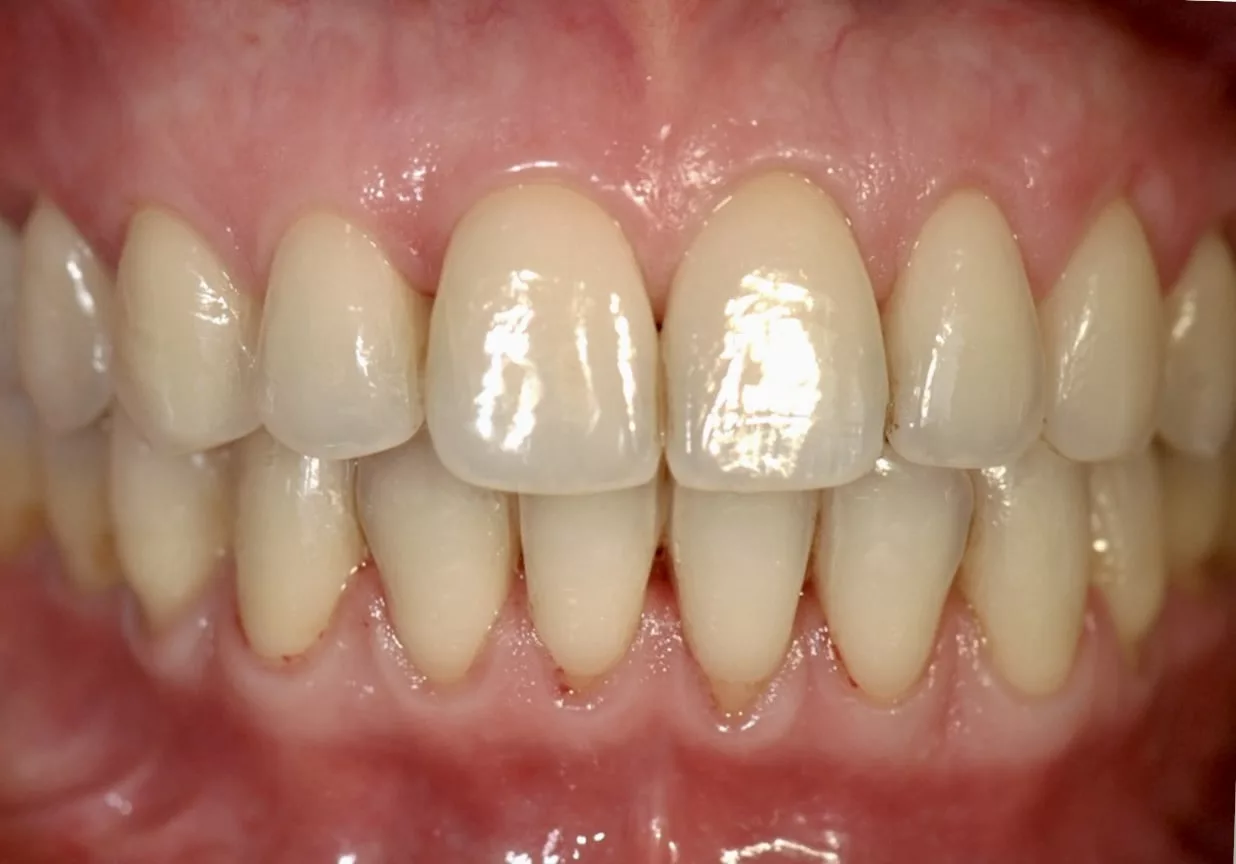

Préalable à tout traitement parodontal, la thérapeutique initiale, non chirurgicale, cherche à décontaminer les surfaces des racines dentaires, et notamment les zones situées sous la gencive. En effet les bactéries adhèrent très fortement à ces régions. Leur persistance, si elles ne sont pas rapidement éliminées, produit un effet pathogène (inflammation, abcès) pour les tissus de support des dents (gencive et tissu osseux).

Une anesthésie locale pourra être administrée afin d’améliorer le confort du patient.

En cas de mobilité dentaire prononcée, des contentions pourront être réalisées afin d’immobiliser les dents concernées et apporter un confort de vie au patient.